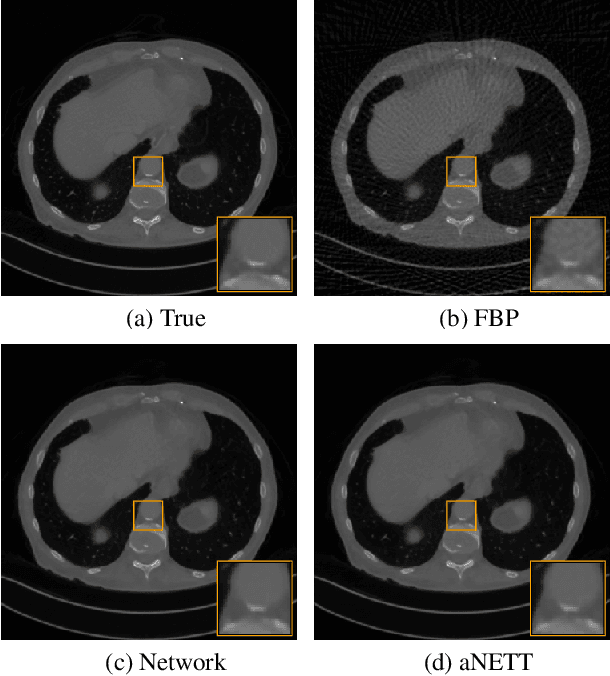

Abstract:We propose a sparse reconstruction framework (aNETT) for solving inverse problems. Opposed to existing sparse reconstruction techniques that are based on linear sparsifying transforms, we train an autoencoder network $D \circ E$ with $E$ acting as a nonlinear sparsifying transform and minimize a Tikhonov functional with learned regularizer formed by the $\ell^q$-norm of the encoder coefficients and a penalty for the distance to the data manifold. We propose a strategy for training an autoencoder based on a sample set of the underlying image class such that the autoencoder is independent of the forward operator and is subsequently adapted to the specific forward model. Numerical results are presented for sparse view CT, which clearly demonstrate the feasibility, robustness and the improved generalization capability and stability of aNETT over post-processing networks.